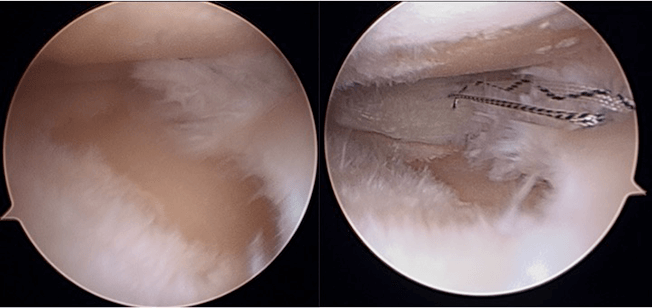

我々は、軟骨機能を温存するため、inside-out法による強固な縫合を、関節鏡を用いて行っております。より強固に縫合するため特殊な縫合方法で行っております。下肢アライメント不良がある膝に対しては、アライメント矯正手術を併用した半月板縫合術も行う場合もあります。